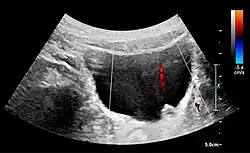

With US, larger stones (>5–7 mm) within the kidney, i.e., in the calyces, the pelvis and the pyeloureteric junction, can be differentiated, especially in the cases with accompanying hydronephrosis (Figure 18 and Figure 19). Hyperechoic stones are seen with accompanying posterior shadowing. Additional twinkling artifacts below the stone can often be seen using Doppler US. Large stones filling the entire collecting system are called coral stones or staghorn calculi and are easily visualized with US (Figure 20). Stones in the ureters are usually not visualized with US due to the air-filled intestines obscuring the insonation window. However, ureteral stones near the ostium can be visualized with a scan position over the bladder. An exam of the ureteric orifices and the excretion of urine to the bladder can be performed by inspecting the ureteric jets in the bladder with color Doppler US.

Figure 21. Left hydroureter with ureteric jet. No stone is visible. The red color in the color box represents motion towards the transducer as defined by the color bar.[1]